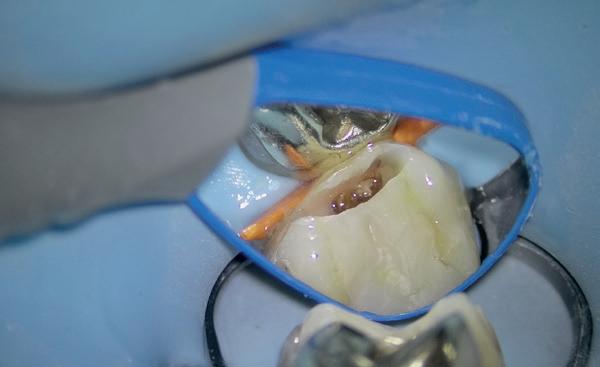

Het isoleren van het werkgebied is belangrijk. Op deze manier krijgt de behandelaar meer controle over het werkgebied en is werken onder microscopisch zicht mogelijk. Eventueel kan er gebruik gemaakt worden van de ‘split dam techniek’, zodat het subgingivale gebied toegankelijker is. Het (opnieuw) plaatsen van het cofferdamvel na preparatie is ook een mogelijkheid (afbeelding 1 en 2).

Stap 2: Preparatie van element en gingiva

Verwijder carieus tandweefsel en maak bij twijfel gebruik van een cariësdetector. In veel gevallen zal het voorkomen dat je subgingivaal eindigt. Gingiva dat in de preparatie ligt kun je verwijderen met bijvoorbeeld een elektrotoom. Ikzelf maak gebruik van

een draadloze warmtespreader, de Superendo Alpha (afbeelding 3 en 4).